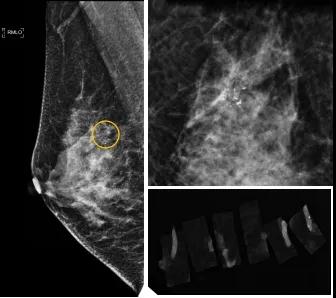

46歲的某女士在西安國際醫(yī)學中心醫(yī)院體檢時,行乳腺X線攝影(俗稱鉬靶)發(fā)現右乳可疑簇狀鈣化,分布范圍不到1厘米,臨床觸不到,超聲很難發(fā)現,但是這種鈣化風險比較高,依據國際BI-RADS指南需要明確病理!

西安國際醫(yī)學中心醫(yī)院影像診療中心陳寶瑩副主任帶領的團隊,采用全數字化乳腺X線三維立體定位系統(tǒng)可實施。這個團隊的成員大部分來自知名三甲醫(yī)院,有著十余年影像引導下乳腺介入診療的經驗,X線引導穿刺定位和活檢例數居西北前列。為減少患者創(chuàng)傷,在詳細判讀了患者資料,并與患者及甲乳外科劉曉敏主任充分溝通的基礎上,團隊確定采用全數字化乳腺X線三維立體定位系統(tǒng)下實施粗針活檢。

當天,乳腺X線三維立體定位系統(tǒng)清晰顯示出了所有鈣化。為了獲取充足的組織量,保證病理診斷的準確性,團隊選用14G穿刺針并多點、多角度取材,組織取出后,又立即在高清標本攝影系統(tǒng)中進行投照,從而確定了取出組織中具有足夠的可疑鈣化。整個過程患者無任何不適,活檢結束后即回家觀察。